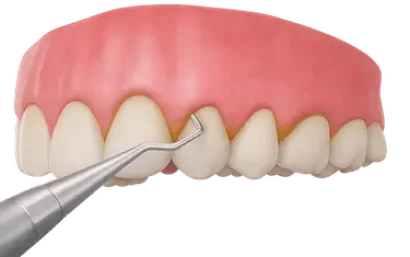

Curetaje, raspado o alisado radicular

El curetaje dental, raspado o alisado radicular es el tratamiento destinado a eliminar la placa bacteriana, es decir, el depósito duro también conocido como cálculo o sarro que se acumula en la base del diente y bajo las encías.

Este sarro es el principal responsable de la enfermedad periodontal.